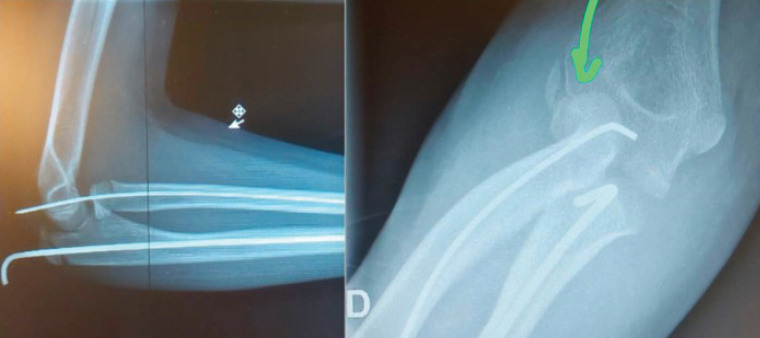

Introduction: Association of elbow dislocation, radial neck fracture (RNF), and ulnar shaft fracture has not been reported previously in the pediatric population.

Case report: This 11-year-old girl fell from her height. She presented a severely displaced RNF, a greenstick fracture of the proximal ulnar shaft, and a posterior elbow dislocation.

Conclusion: This article describes a very rare case, shows a possible treatment, and presents the follow-up with a final good result.